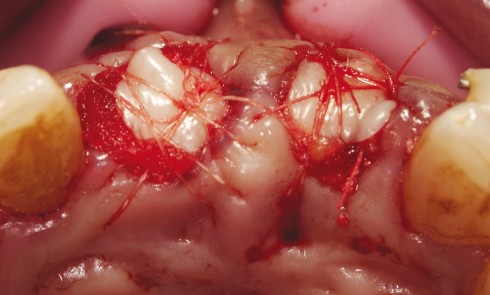

Article réservé à nos abonnés Extraction d’une dent délabrée non conservable et aménagement d’un site implantaire

Lors de l’extraction d’une dent, il est important de préserver les tissus muqueux et osseux environnants, tout d’abord pour limiter...